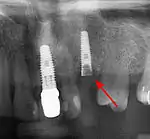

Long-term failures are due to either loss of bone around the tooth and/or gingiva due to peri-implantitis or a mechanical failure of the implant. Because there is no dental enamel on an implant, it does not fail due to cavities like natural teeth. While large-scale, long-term studies are scarce, several systematic reviews estimate the long-term (five to ten years) survival of dental implants at 93–98 percent depending on their clinical use.[2][3][4] During initial development of implant retained teeth, all crowns were attached to the teeth with screws, but more recent advancements have allowed placement of crowns on the abutments with dental cement (akin to placing a crown on a tooth). This has created the potential for cement, that escapes from under the crown during cementation to get caught in the gingiva and create a peri-implantitis (see picture below). While the complication can occur, there does not appear to be any additional peri-implantitis in cement-retained crowns compared to screw-retained crowns overall.[75] In compound implants (two stage implants), between the actual implant and the superstructure (abutment) are gaps and cavities into which bacteria can penetrate from the oral cavity. Later these bacteria will return into the adjacent tissue and can cause periimplantitis.